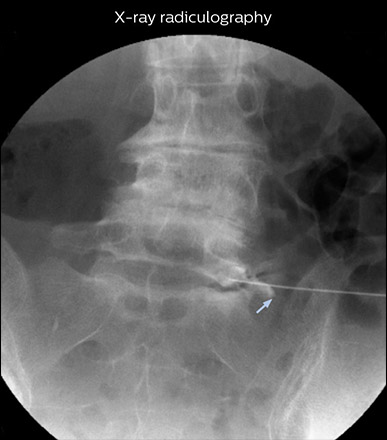

“In such case, we would then browse through axial T2-weighted MR images slice by slice and mentally reconstruct the actual situation based on both radiculography and MRI. Fortunately, NerveVIEW can now very well show nerve courses and presence of nerve compression or edema in one single image series.” “We have often seen NerveVIEW directly depict details of the nerve compression that were not observed by radiculography. Therefore, we think that with NerveVIEW we can reduce the number of invasive examinations, especially for some patients with lumbar plexus symptoms.”

“Before NerveVIEW, diagnosis by MRI alone was sometimes difficult, unless there was a strong suspicion based on clinical symptoms,” says Shoji Yabuki, MD, DMSc, Orthopedic surgeon at Fukushima Medical University School of Medicine. “This is why we routinely perform selective lumbosacral radiculography (nerve root block) and x-ray in such cases. However, radiculography can only depict nerves as far as the contrast agent reaches. When a nerve is distorted by compression, the contrast agent will not pass through this compressed area, preventing us from evaluating the full nerve compression.”